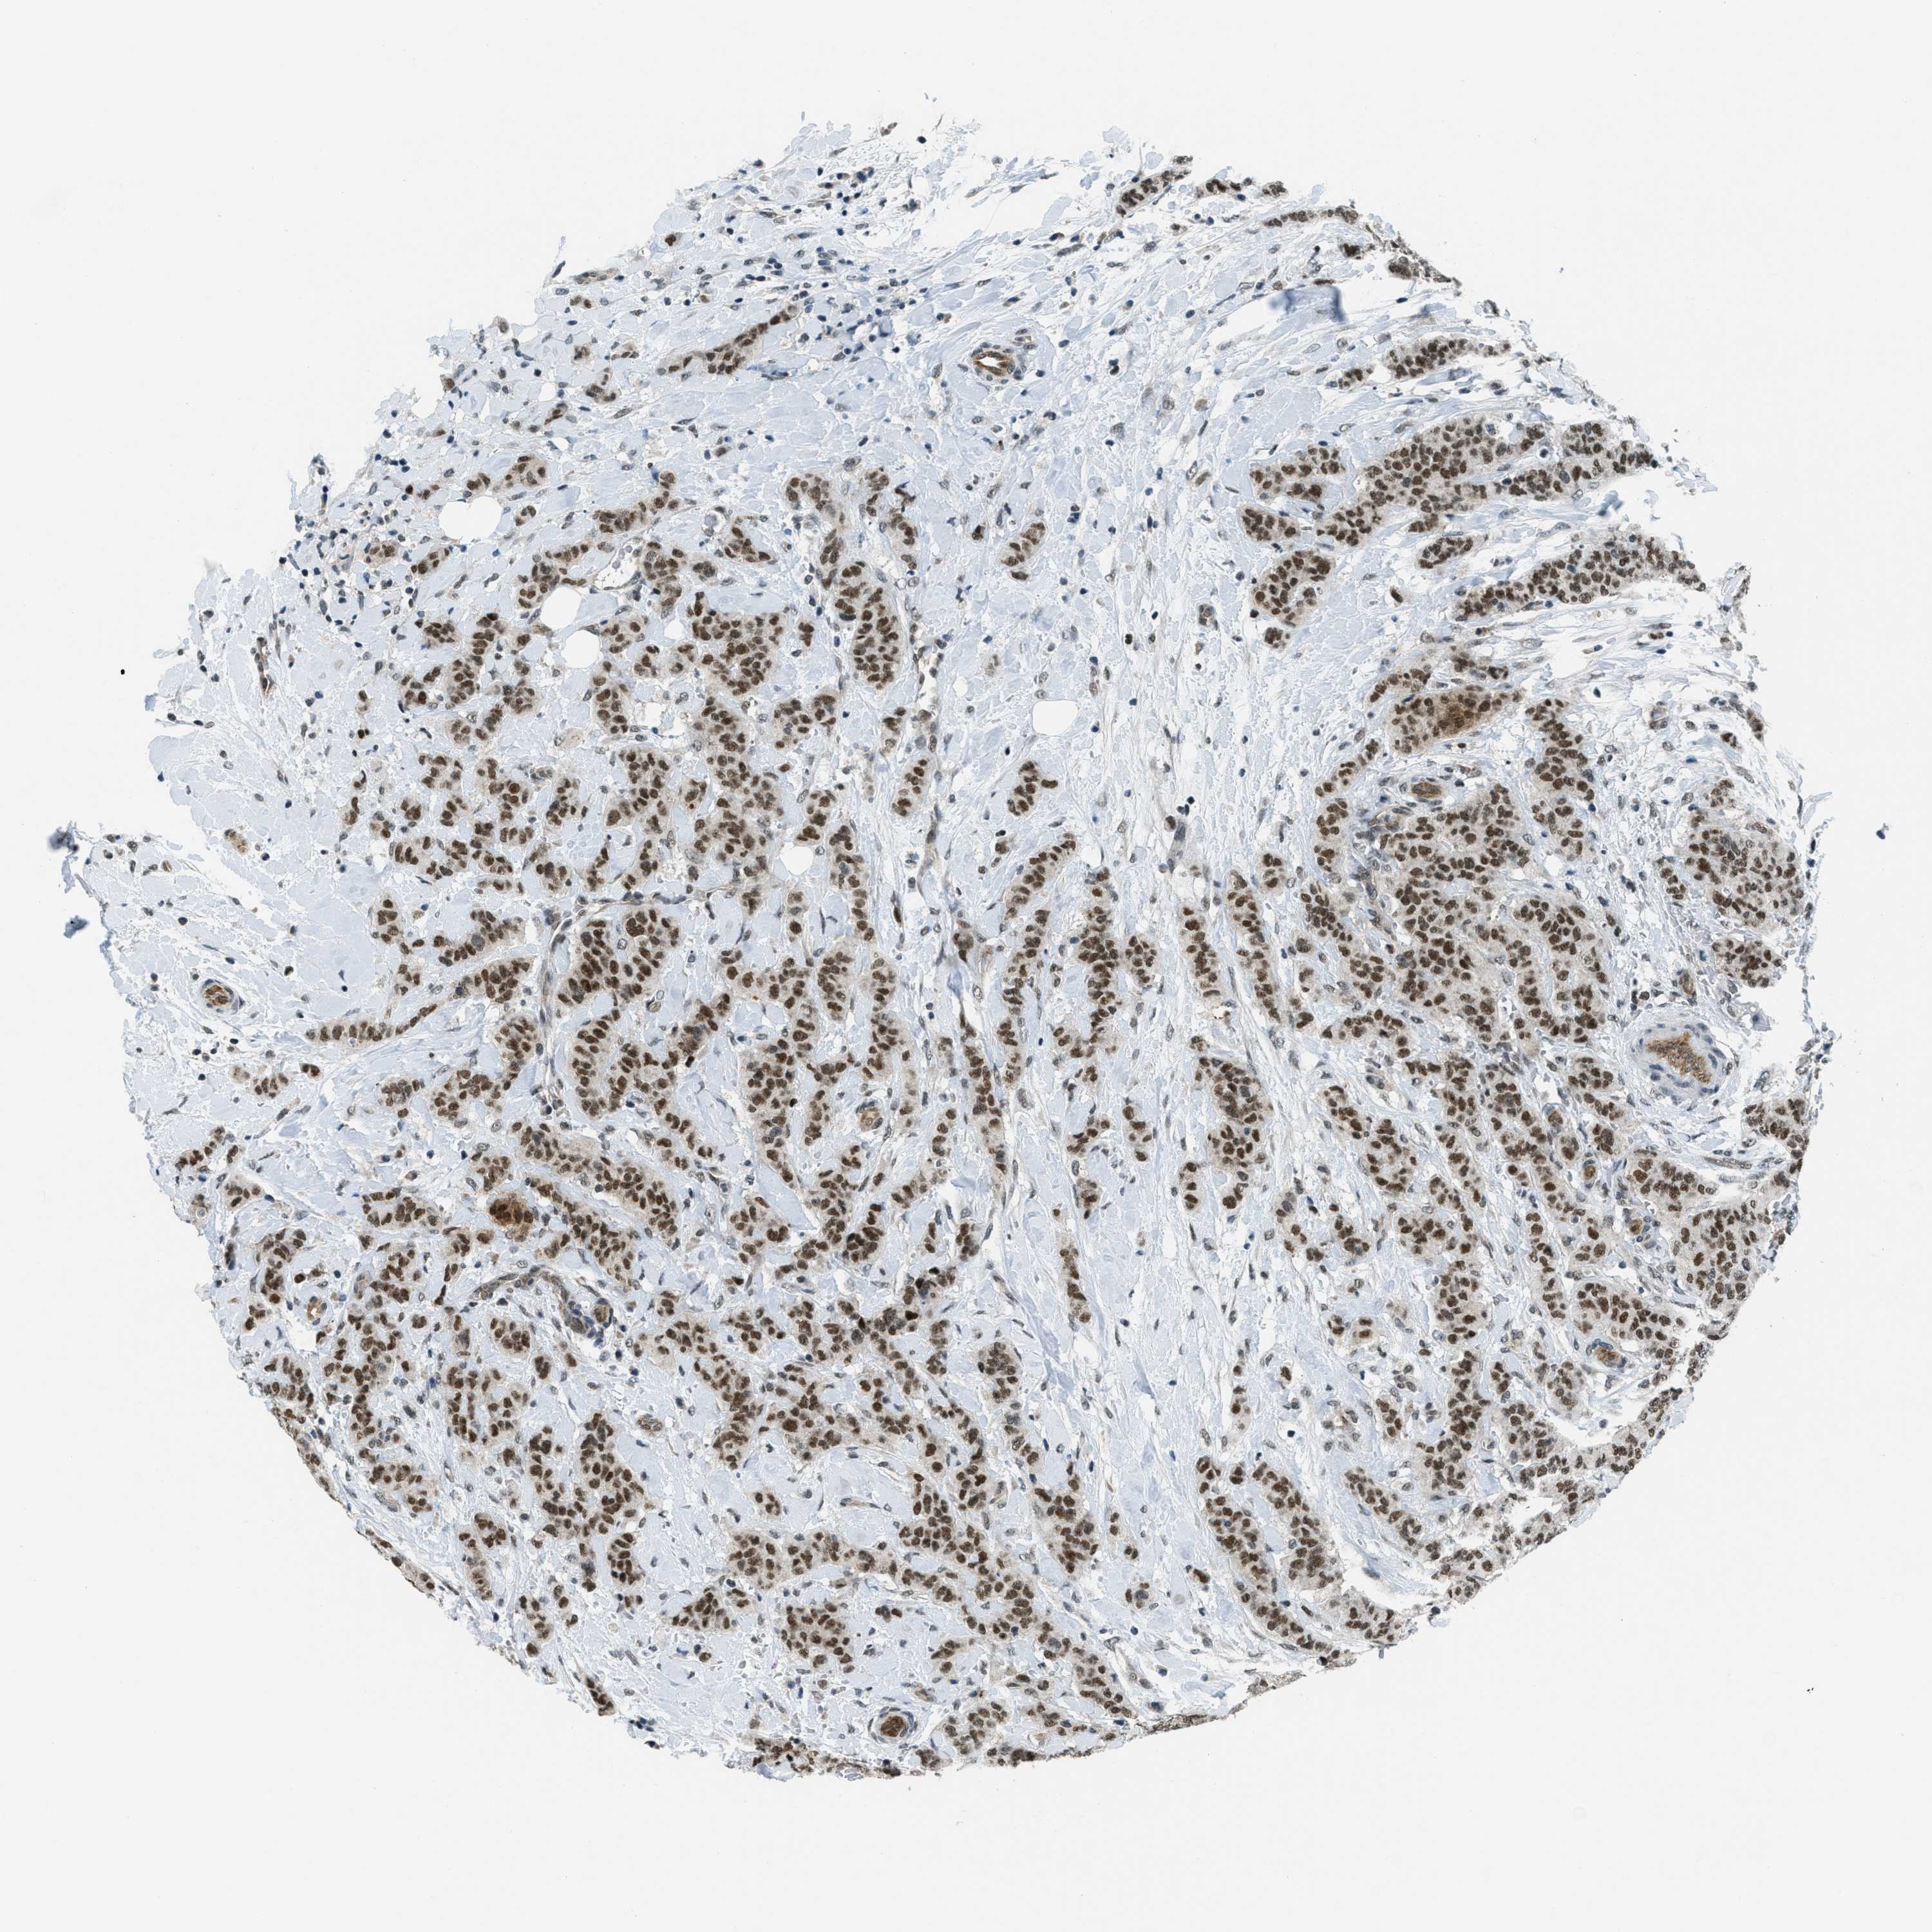

CANCER BREAST CANCER Show tissue menu

BRCA TCGA BRCA VALIDATION PROTEIN EXPRESSION